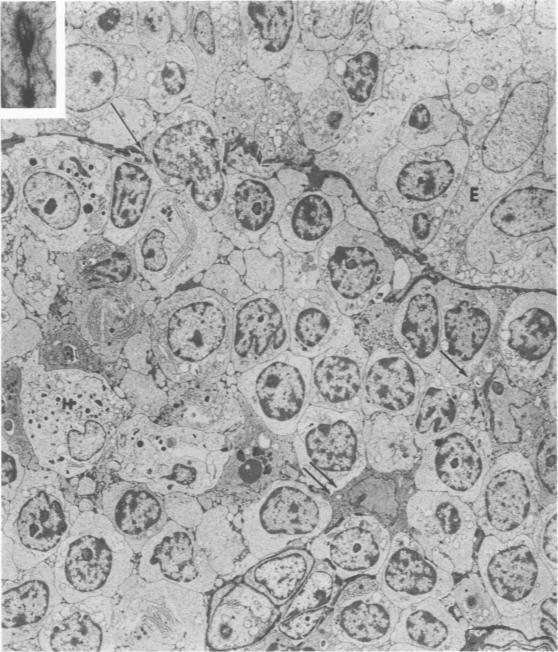

In this study, thymoma is defined as a neoplasm of the epithelial-reticular framework cells of the thymus. As in the normal thymus, these cells regularly displayed branching tonofilaments, macuale adherens, elongated processes, and basal lamina. These characteristics proved useful in the differential diagnosis of thymoma from a variety of anterior mediastinal tumors including thymic carcinoid, lymphoma, germinoma (seminoma type), and fibrous mesothelioma. Lymphocytes in the thymomas often showed mitotic activity and a moderate degree of transformation. The significance of this and the gland-like spaces, vacuolated epithelial cells, starry-sky appearance, emperipolesis, and perivascular spaces is discussed.